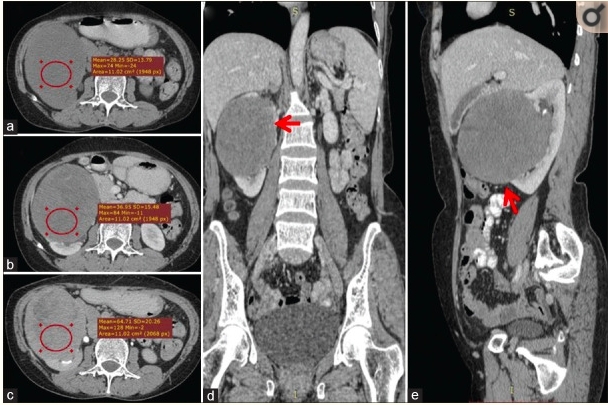

腹部超声显示右肾上极和中极有一个大的异质性高回声占位性病变。对腹部进行了对比增强计算机断层扫描,发现右肾上极和中极有一个大小为12cm×10cm的不均匀强化肿块,累及肾窦。肾静脉未见癌栓(图1)。附近的组织没有被累及。进行转移性检查(肝功能、血清碱性磷酸酶和胸部X光检查),结果均在正常范围内。建议患者接受开放性右侧根治肾切除术。术中,肿块紧贴肝脏,从中仔细解剖。肾动脉被双重结扎并分开,然后以相同的方式处理肾静脉。将根治性肾切除标本送去组织病理学检查。术后过程平稳,术后4天患者出院。

图1. 右肾有一巨大、包裹良好的肿块,起源于前皮质,累及肾窦。